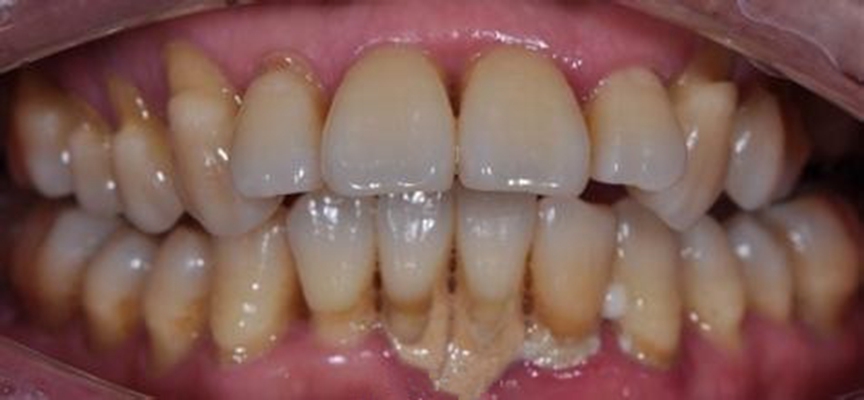

牙周炎圖片

牙周袋 (7)